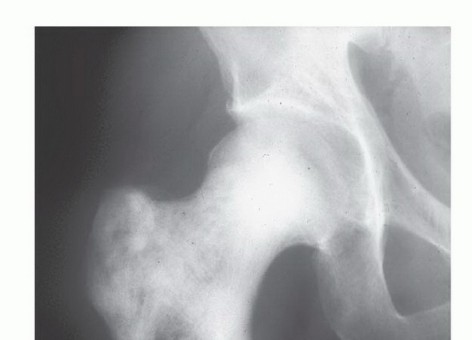

الشكل 1: أ. صورة أشعة سينية تظهر ورمًا نقيليًا في الحُق الأيمن لدى رجل يبلغ من العمر 72 عامًا ولديه تاريخ معروف بسرطان الغدة الدرقية. ب. يظهر التصوير المقطعي المحوسب (CT) تدميرًا واسعًا للعظام وامتدادًا للأنسجة الرخوة. محاولة الاستئصال بناءً على النتائج الشعاعية وحدها قد تؤدي إلى استئصال جزئي للآفة ونزيف محتمل بسبب الأوعية الدموية الكثيفة لهذا الورم. بالنظر إلى هذه النتائج الشعاعية، خضع هذا المريض لانسداد وعائي قبل الجراحة مما قلل من فقدان الدم أثناء الجراحة وسمح باستئصال ناجح.